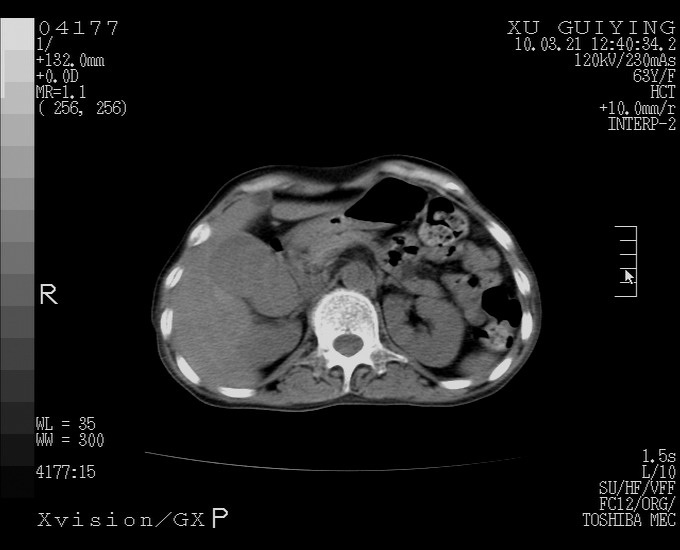

胆囊体积增大,胃窦壁增厚

胆囊体积增大,密度不均匀,结石不除外;胃壁增厚,考虑胃癌,建议增强。

胆囊体积增大,密度增高,较均匀,外缘也较光滑,应考虑胆囊炎。因为胃未充盈,不好说壁增厚。肝左叶及脾门处见低密度灶,有可能是血管瘤,不排除囊肿。建议超声检查或强化。

这就是江湖人称的“内科黄疸”, 肝内胆汁淤积症(ic)?